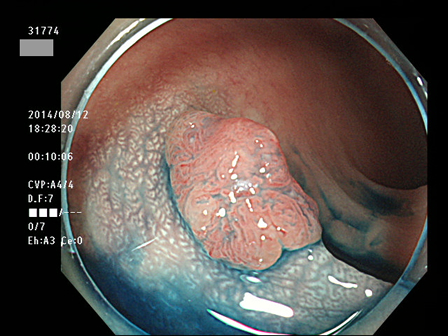

上記100名より抽出した平坦・陥凹型腺腫(=癌化の危険が高いが見落としやすい病変)の内視鏡写真

31764 31765 31766 31767 31768 31769 31771 31774 31776 31777 31778 31779